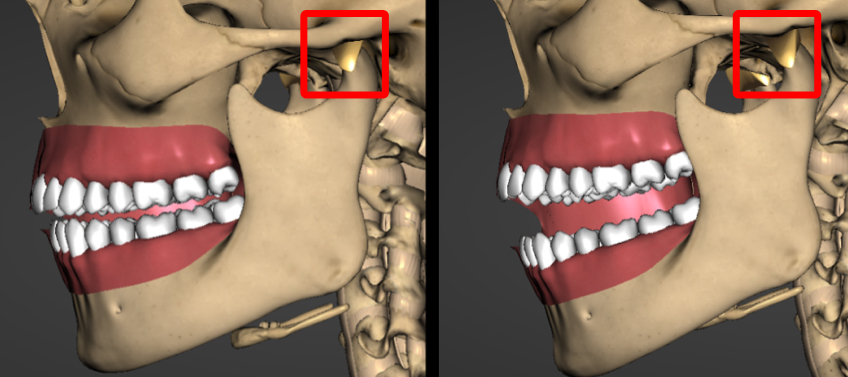

- When the loss of vertical dimension is bilateral, it results in a Class II mandibular shift and a retrognathic profile.

- If the loss of vertical dimension is unilateral, it also causes a Class II shift and may affect the horizontal occlusal plane.

Differences in condylar heights often influence the maxillary arch, leading to an occlusal cant or a stepped occlusal plane (Fig. 5).

A Class II occlusal relationship often causes an excessive overjet, making it difficult to establish anterior guidance and resulting in excessive wear on posterior teeth. When the maxillary and mandibular teeth are assessed in the fully seated condylar position, the first point of contact is usually on the second molars or the most distal teeth. If a patient functions in the retruded position, it can increase stress on the tooth structure or restorations.